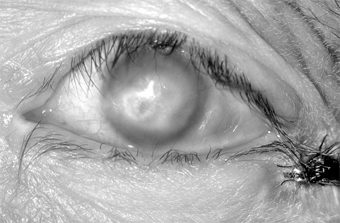

A molluscum nodule on the lid margins or the skin of the lids or brow may produce unilateral chronic follicular conjunctivitis, superior keratitis, and superior pannus and may resemble trachoma. The inflammatory reaction is predominantly mononuclear (unlike the reaction in trachoma), and the round, waxy, pearly-white, noninflammatory lesion with an umbilicated center is typical of molluscum contagiosum (Figure 5-9). Biopsy shows eosinophilic cytoplasmic inclusions that fill the entire cytoplasm of the enlarged cell, pushing its nucleus to one side.

Figure 5-9

Figure 5-9: Molluscum contagiosum of lid margin. Follicular conjunctivitis was present.